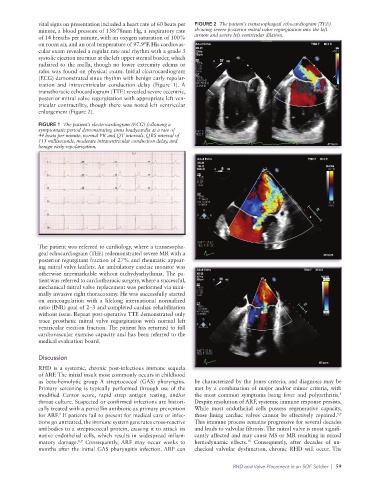

vital signs on presentation included a heart rate of 60 beats per FIGURE 2 The patient’s transesophageal echocardiogram (TEE)

minute, a blood pressure of 138/78mm Hg, a respiratory rate showing severe posterior mitral valve regurgitation into the left

of 14 breaths per minute, with an oxygen saturation of 100% atrium and severe left ventricular dilation.

transthoracic echocardiogram (TTE) revealed severe eccentric,

posterior mitral valve regurgitation with appropriate left ven-

tricular contractility, though there was noted left ventricular

enlargement (Figure 2).

The patient was referred to cardiology, where a transesopha-

geal echocardiogram (TEE) redemonstrated severe MR with a

posterior regurgitant fraction of 27% and rheumatic appear-

ing mitral valve leaflets. An ambulatory cardiac monitor was